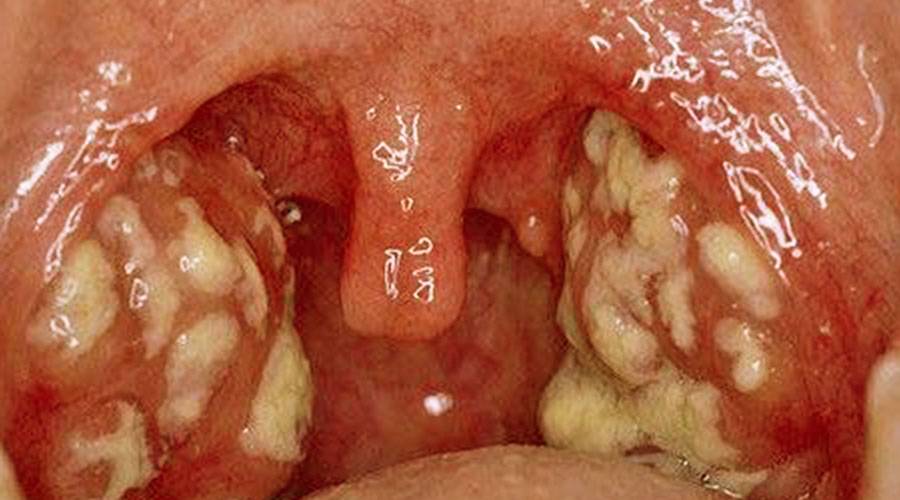

Лакунарная ангина у взрослых — протекает тяжелее, чем фолликулярная. Общие симптомы ангины такие же, только значительно выраженные. Нёбо приобретает ярко-красный цвет, на миндалинах отмечается налёт жёлтого цвета. В редких случаях температура поднимается до 40° С.

Фиброзная ангина — является осложненным случаем двух предыдущих вариантов. Для ней характерен единый сплошной налёт бело-желтого цвета, который может выходить за пределы миндалин.

Флегмонозная

Флегмонозная ангина — обычно развивается как продолжение фиброзной формы. Пациента беспокоит резкая невыносимая боль в горле, которая чаще всего бывает односторонней. Больному тяжело открывать рот, разговаривать, голос становится гнусавым. Появляется специфический запах изо рта, напоминающий запах ацетона. Температура повышается до 40 C. Миндалина покрыта серовато-желтым налетом, отечна, на ощупь болезненная.